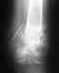

СРОЧНО нуждаемся в Вашей помощи.Диагноз: Открытый многоосколочный перелом - вывих III-В типа, проксимального эпиметафиза правой плечевой кости со смещением и дефектом костной ткани.

Перелом акромиального отростка справа со смещением, перелом тела лопатки справа без смещения.Послеоперационный период усложнился нагноением гематомы. Операция была проведена 16.11.2005года.Очень ждём Вашего ответа.Большое СПАСИБО!

Пациент находится в условия больницы или дома? Если дома - надо в гнойное отделение. Если в больнице, то чем обусловлен вопрос? Не видя снимков и фото сегмента сейчас, трудно что-то определенное советовать. Так, вообще - аппарат внешней фиксации по крайней мере до купирования гнойного процесса, повторные санации гнойного очага, возможно, спейсер из костного цемента с антибиотиками.